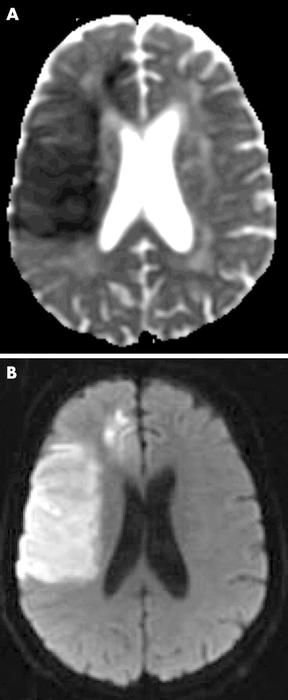

Apparent diffusion coefficient (ADC) map and diffusion weighted MRI (DWI) of subacute stroke (day 3). Restricted diffusion of water leads to decreased signal on ADC, increased signal on DWI

Muir KW et al. Neuro 2005; 76: iii19-iii28; used with permission